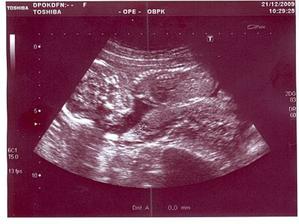

*21.12.2009 ... 19+5 tt, velký UTZ ve 20tt (mimi odpovídá 19+4tt, vše v pořádku!, dozvěděli jsme se pohlaví)